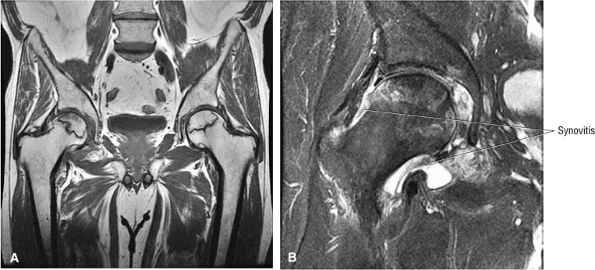

FIGURE 3.85 ● Coronal T1 FSE (A) and FS PD FSE (B) images showing AVN with associated synovitis. The central AVN focus demonstrates marrow fat signal intensity. Synovitis demonstrates intermediate signal intensity.

FIGURE 3.86 ● AVN associated with acetabular degenerative changes. Note the hypointense sclerotic reaction of the femoral head. (A) Coronal T1-weighted image. (B) Coronal FS PD FSE image.